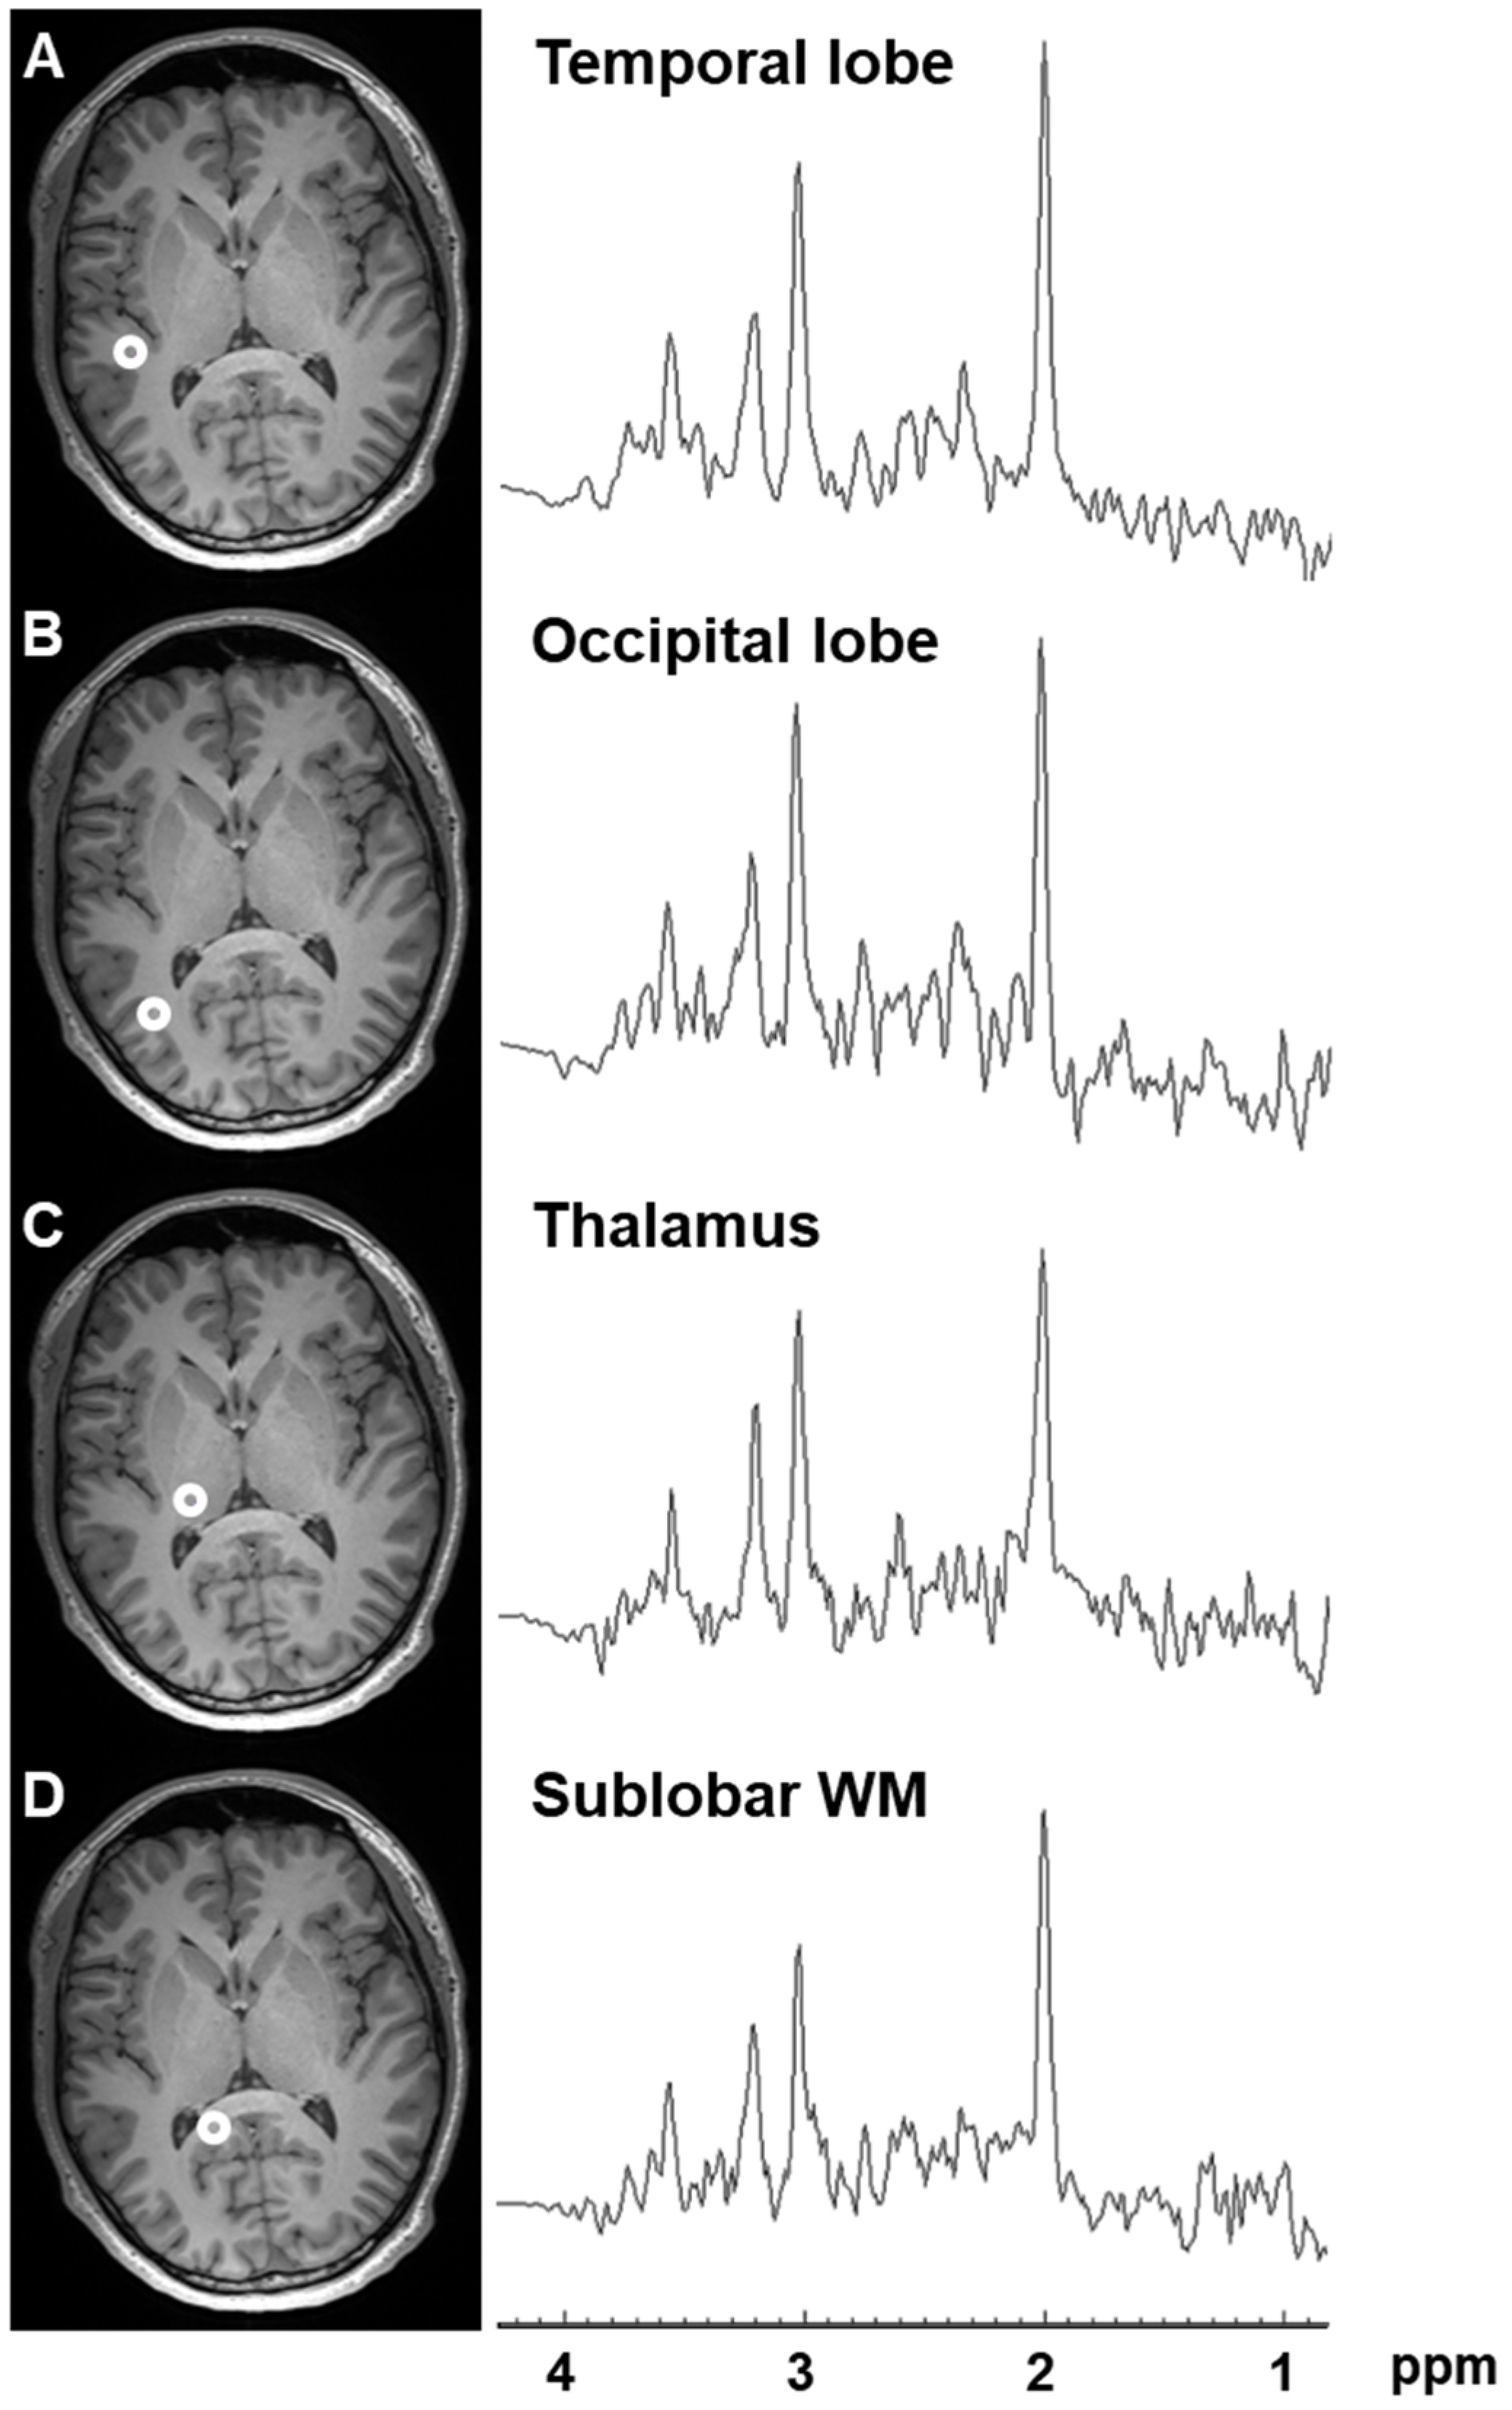

2.1. Variation in Metabolite Ratios with Anatomical Location